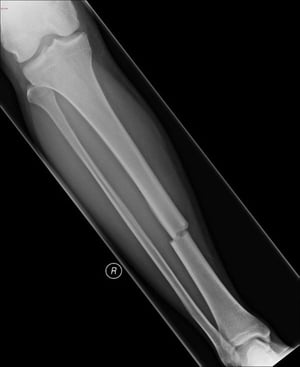

Поперечний перелом діафізу великогомілкової кістки

Такий поперечний перелом уражає середню частину великогомілкової кістки.

Знімок люб'язно надано лікарем Даніелем Кампаньє [Danielle Campagne], MD.